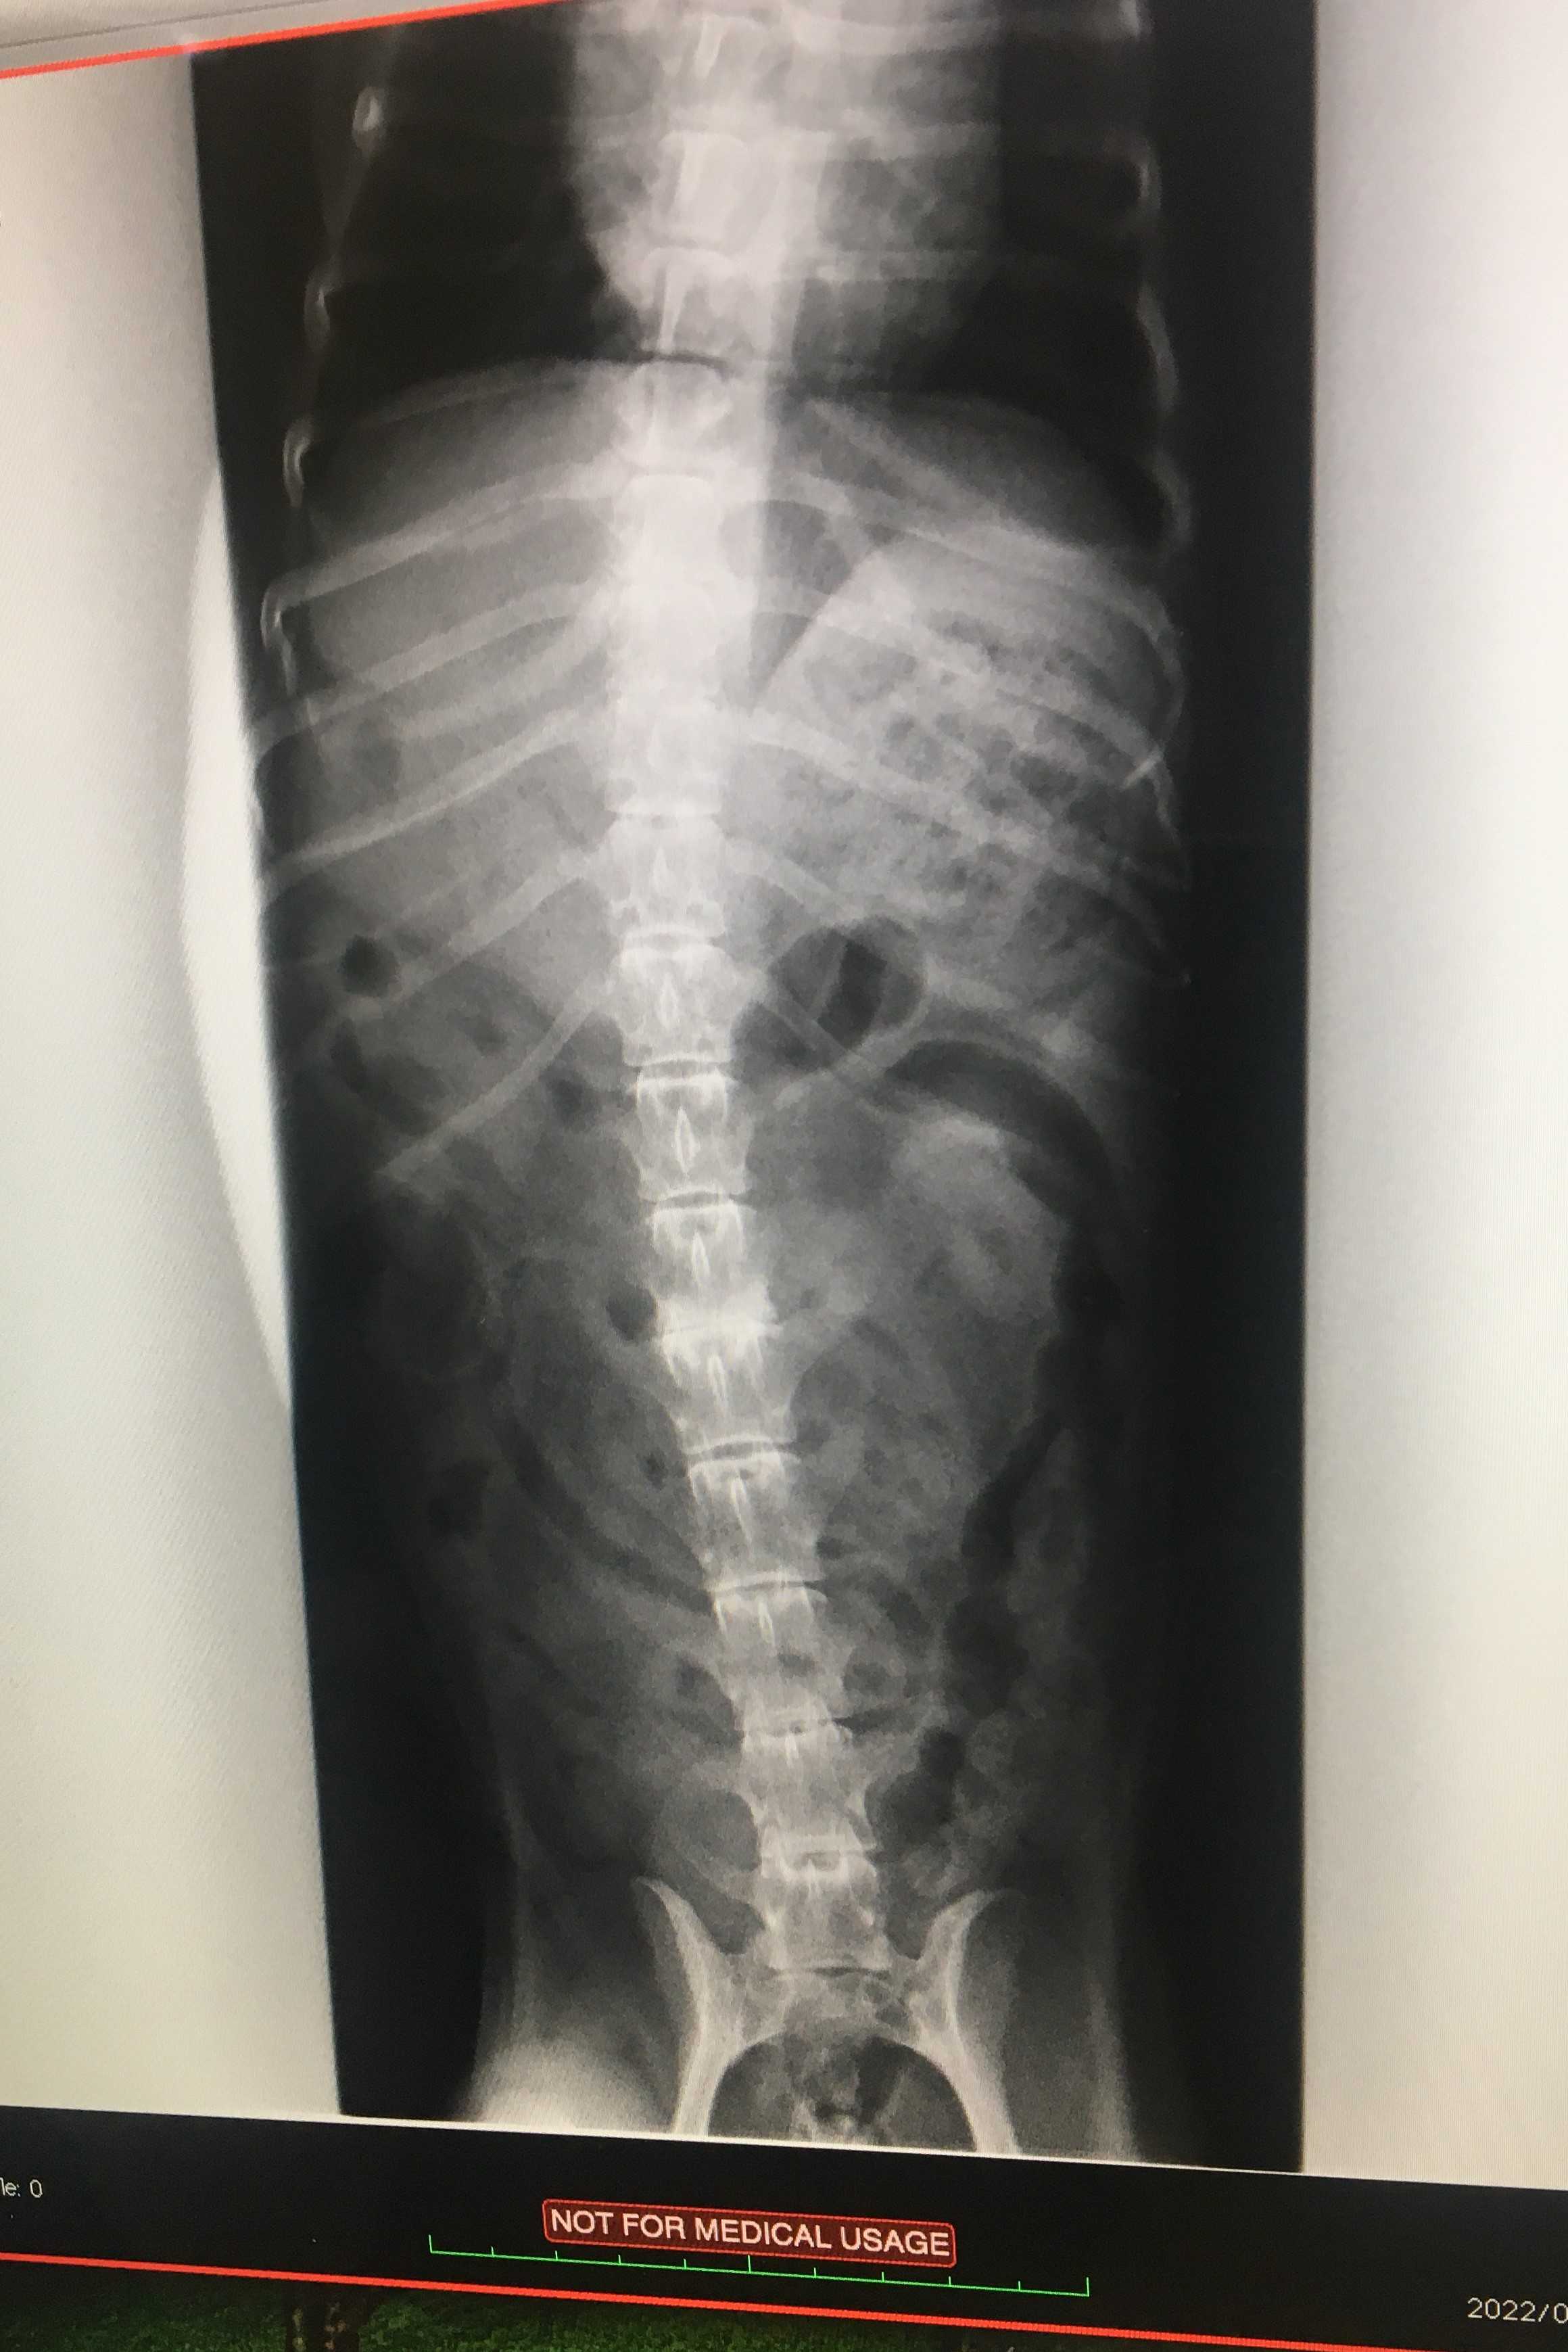

レントゲンの画像がありますので苦手な方はご遠慮ください

こちら2月に撮ったレントゲンですね

で、これは今回撮ったものです

異常は無さそうですね

2月のレントゲンもそうなんですけど、白くなってるところは何ですか?

これはヘルニアの痕ですね

症状が出ないまま治ってしまったのでしょう

軟骨部分がすり減った状態です

変形性脊椎症ではないのですか

こちらは違いますね